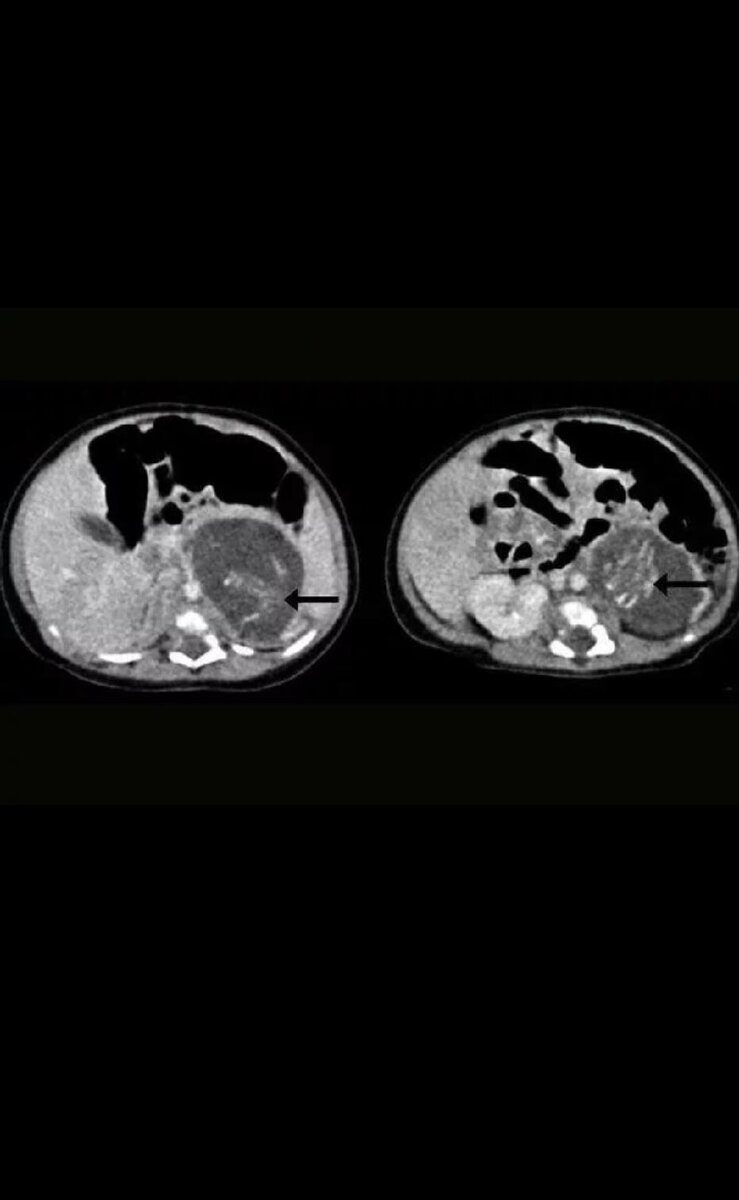

Оба плода были на 8-10-й неделе развития и были соединены с девочкой через пуповину к массе, похожей на плаценту. Их вес составил 14,2 и 9,3 грамма, у них был сформирован позвоночник, ребра, кишечник и даже конечности. И хотя, по словам хирургов, близнецы развивались внутри тела девочки, они были ее единоутробным братом или сестрой.

На фотографии показан позвоночник каждого близнеца